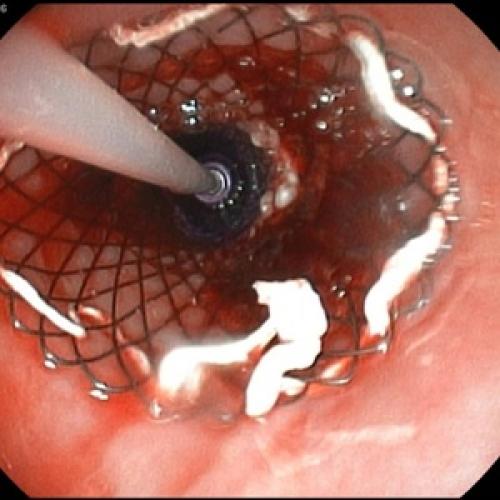

Гастроскопия

Гастроскопия при панкреатите даёт возможность оценить вовлечённость в патологический процесс желудка и двенадцатиперстной кишки. В некоторых случаях с помощью гастроскопии можно установить, что спровоцировало развитие острого воспаления.

Пациентам с предположительным клиническим диагнозом острого панкреатита показано выполнение ЭГДС (дифференциальный диагноз с язвенным поражением гастродуоденальной зоны, осмотр БДС).